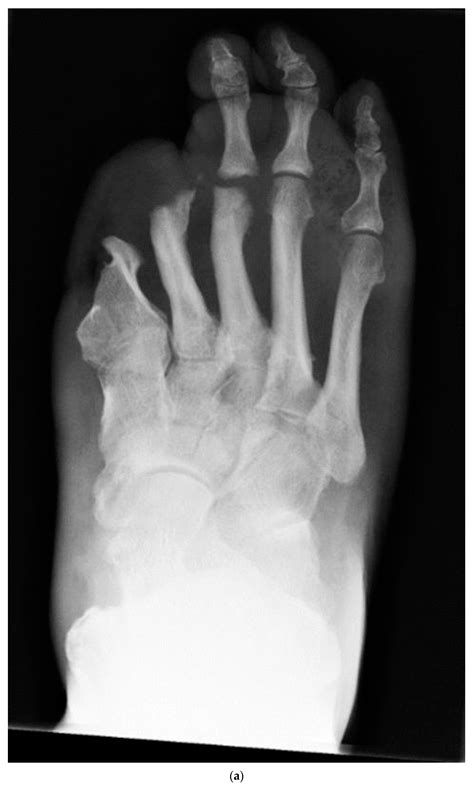

When trauma occurs, the body's natural inflammatory response is triggered. In individuals with neuropathy, this response can be exaggerated, leading to excessive bone resorption and joint destruction. Over time, this process can result in significant deformities, such as a "rocker-bottom" foot, where the arch of the foot collapses, and the sole becomes convex.

• Deformities such as a "rocker-bottom" foot

Imaging studies are essential for confirming the diagnosis and assessing the extent of the condition. Common imaging studies include:

• X-rays: To visualize bone structure and detect any fractures or deformities